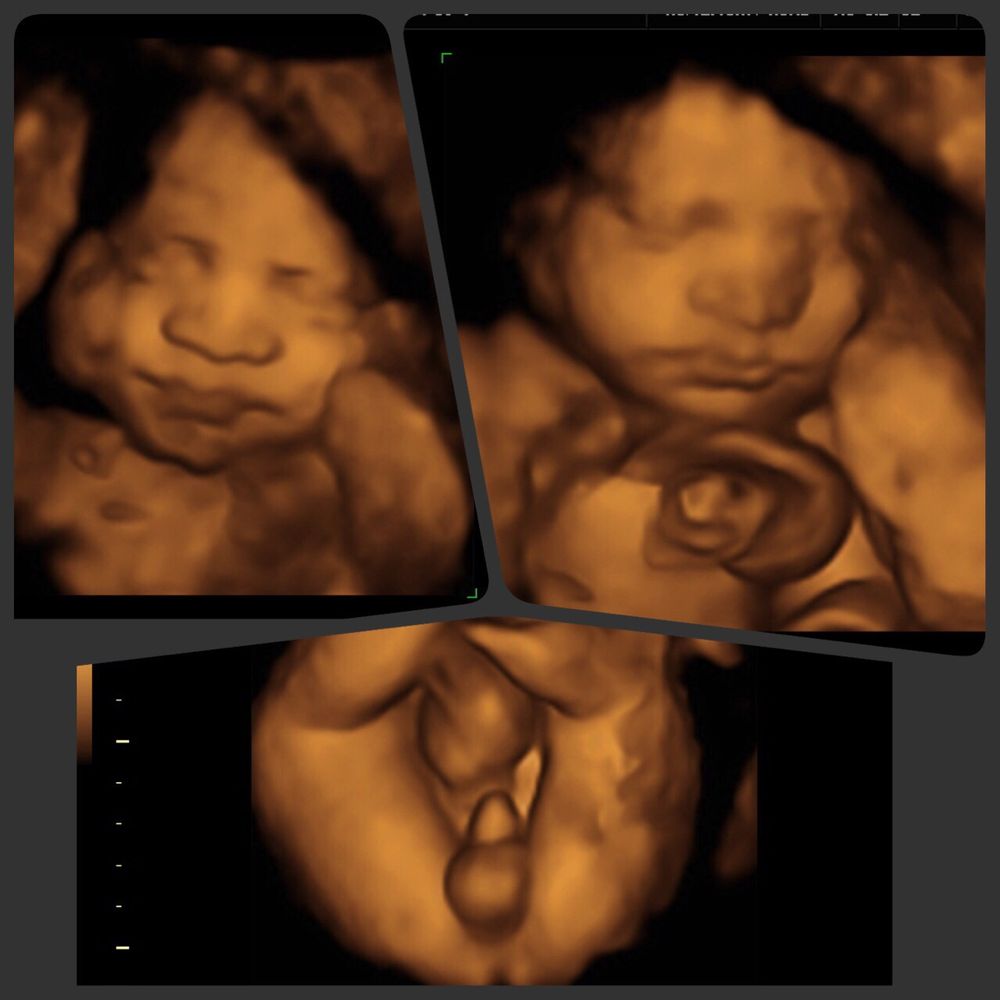

Are 3d And 4d Ultrasounds Harmful To The Baby. My husband really wants us to do one and i�m not sure. Ultrasounds help doctors determine the health,. Are 3d and 4d ultrasounds safe during pregnancy? 3d ultrasound converts sections of 2d images into a 3d picture.

Generally, when administered by a medical practitioner and for medical reasons, they are considered safe. The 4d ultrasound uses sound waves to create this moving image. Studies suggest that 3d and 4d ultrasounds are safe. I keep hearing that is a very special experience but that is also not so great for the baby. Routine scanning of all pregnancies is normal throughout australia. 3d and 4d sltrasounds scans are quite safe and allow parents and doctors to view the baby while it is still in its early stages of development in the womb.

We do not charge an additional fee if you are having twins. As mentioned previously 3d and 4d ultrasounds cannot be done at any time during the pregnancy period. Reasons to get ultrasounds during pregnancy 4d ultrasounds are 3d images in motion. An ultrasound examination is also known as a sonogram.the entire procedure can be performed in 30 minutes or less. This method uses multiple 2d ultrasound images to render a 3d image.

In 3d/4d scanning the same type and intensity of ultrasound is used as with 2d ultrasound. In 3d/4d scanning the same type and intensity of ultrasound is used as with 2d ultrasound. More advanced the stage of pregnancy, higher are the chances of getting clear images of the baby. 3d and 4d sltrasounds scans are quite safe and allow parents and doctors to view the baby while it is still in its early stages of development in the womb. We do not charge an additional fee due to the possibility of not being able to capture images of the second baby.

I copied and pasted this from my local 4d imaging place :) With this technology, you are able to see your baby�s defined facial features. In other words, 3d sonograms and 4d ultrasounds are not part of routine prenatal exams. if your doctor deems a 3d or 4d ultrasound necessary, there�s no cause for concern over the procedure�s safety. Using this technology, you can see what your baby is doing at that moment inside your womb. Ultrasounds have been used for decades in pregnancies.

In simple terms, 3d and 4d ultrasounds are not part of the normal or routine prenatal exams. 4d ultrasound provides moving images as a video and has a higher power output than 2d ultrasound. This method uses multiple 2d ultrasound images to render a 3d image. With these tests, you can see your developing baby on the screen. 3d/4d ultrasounds began to grow in popularity in the early 2000s, and now, the keepsake ultrasound industry, as it�s commonly called, has exploded.

While there is no proof that ultrasounds are harmful to the baby, it heats the baby�s tissues slightly and can also cause small bubbles in tissue; With these tests, you can see your developing baby on the screen. Studies suggest that 3d and 4d ultrasounds are safe. Plus, the images can help doctors spot a problem with your baby and make it easier for them to explain it to you. Using this technology, you can see what your baby is doing at that moment inside your womb.

Studies suggest that 3d and 4d ultrasounds are safe. The 4d ultrasound uses sound waves to create this moving image. An ultrasound examination is also known as a sonogram.the entire procedure can be performed in 30 minutes or less. 3d and 4d scans are usually only available in private clinics. Ultrasounds have been used in pregnancy for decades without any negative effects.

The techs that do the 3d/4d arent required to be certified because it�s not a medical use of the machines. 3d ultrasound technicians are specially trained in prenatal care, so they will also provide you with valuable information on what your baby looks like, its gender, and other vital data that will help you prepare for the arrival of your baby. Ultrasounds have been used in pregnancy for decades without any negative effects. Studies have found no link between ultrasound and birth weight, childhood cancers, dyslexia, or problems with eyesight or hearing (van den. 3d ultrasound converts sections of 2d images into a 3d picture.

As mentioned previously 3d and 4d ultrasounds cannot be done at any time during the pregnancy period. So the power intensity is the same as it is for 2d scanning over a few seconds. A 4d ultrasound is similar to a 3d ultrasound, but the image shows movement like a video would. An ultrasound examination is also known as a sonogram.the entire procedure can be performed in 30 minutes or less. Ultrasound scans are safe for your baby.

3d and 4d ultrasounds are considered safe, as long as they’re conducted by a certified. This method uses multiple 2d ultrasound images to render a 3d image. Studies suggest that 3d and 4d ultrasounds are safe. 3d and 4d ultrasounds are considered safe, as long as they’re conducted by a certified. Ultrasounds have been used for decades in pregnancies.

3d and 4d sltrasounds scans are quite safe and allow parents and doctors to view the baby while it is still in its early stages of development in the womb. 3d and 4d ultrasounds are considered safe, as long as they’re conducted by a certified. We do not charge an additional fee if you are having twins. Studies suggest that 3d and 4d ultrasounds are safe. In simple terms, 3d and 4d ultrasounds are not part of the normal or routine prenatal exams.

The test does not involve radiation and is completely safe for both mother and baby. Routine scanning of all pregnancies is normal throughout australia. In other words, 3d sonograms and 4d ultrasounds are not part of routine prenatal exams. if your doctor deems a 3d or 4d ultrasound necessary, there�s no cause for concern over the procedure�s safety. There’s no evidence that ultrasounds are harmful, if they are performed correctly (health canada 2013, salem et al 2014, sogc 2019, van den hof 2018). 4d ultrasounds are 3d images in motion.

In other words, 3d sonograms and 4d ultrasounds are not part of routine prenatal exams. if your doctor deems a 3d or 4d ultrasound necessary, there�s no cause for concern over the procedure�s safety. This method uses multiple 2d ultrasound images to render a 3d image. 3d ultrasound converts sections of 2d images into a 3d picture. In simple terms, 3d and 4d ultrasounds are not part of the normal or routine prenatal exams. She said that the recommended level of ultrasound machines is at 50% but the default when turning the machines on is 100% and that some 3d/4d places dont change the setting and therefore it can be harmful to the baby.

3d ultrasounds are not harmful to the baby, and there is no risk for the mother or child. Vegas baby experience the full house. When having twins, we do recommend a 3d/4d ultrasound at 25 weeks. Plus, the images can help doctors spot a problem with your baby and make it easier for them to explain it to you. 4d ultrasounds are 3d images in motion.

They include the quick look. With these tests, you can see your developing baby on the screen. Vegas baby experience the full house. Moreover, 3d or 4d ultrasound can effectively detect birth defects which otherwise may not appear on a 2d ultrasound. So the power intensity is the same as it is for 2d scanning over a few seconds.

With these tests, you can see your developing baby on the screen. 3d and 4d ultrasounds are considered safe, as long as they’re conducted by a certified. Ultrasounds have been used in pregnancy for decades without any negative effects. While there is no proof that ultrasounds are harmful to the baby, it heats the baby�s tissues slightly and can also cause small bubbles in tissue; At the moment there exists no reliable evidence showing that ultrasound is harmful to you or the baby.

So the power intensity is the same as it is for 2d scanning over a few seconds. A 4d ultrasound is similar to a 3d ultrasound, but the image shows movement like a video would. Are 3d and 4d ultrasounds safe during pregnancy? Routine scanning of all pregnancies is normal throughout australia. Generally, when administered by a medical practitioner and for medical reasons, they are considered safe.

Are 3d/4d ultrasounds harmful for baby? Ultrasounds help doctors determine the health,. Click to see all packages. 4d scans show moving 3d images of your baby, with time being the fourth dimension. That said, the concern for doctors is with companies that offer keepsake ultrasounds.

Ultrasound scans are safe for your baby. Click to see all packages. I keep hearing that is a very special experience but that is also not so great for the baby. In 3d/4d scanning the same type and intensity of ultrasound is used as with 2d ultrasound. A 4d ultrasound is similar to a 3d ultrasound, but the image shows movement like a video would.